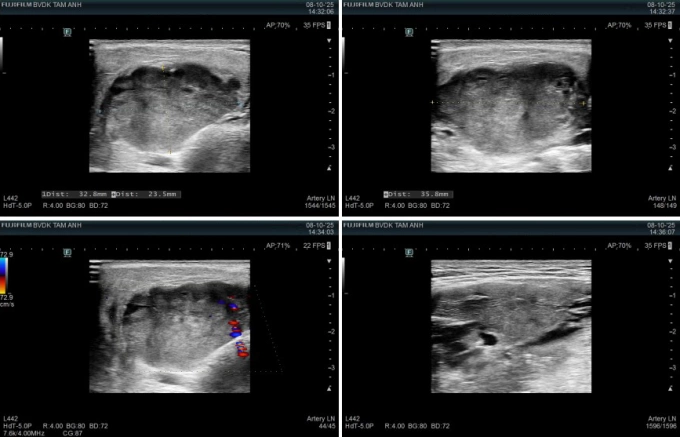

Kết quả chụp chiếu vùng mang tai và cổ cho thấy u tuyến mang tai trái kích thước 29×15 mm, ranh giới rõ, bờ cong đều, không vôi hóa. Các tuyến nước bọt khác và hạch vùng cổ bình thường, chưa ghi nhận dấu hiệu viêm hay di căn. Bác sĩ còn phát hiện một vài nhân nhỏ ở tuyến giáp hai bên, kích thước lớn nhất 22×13 mm, lành tính.

Tương tự, anh Thành, 31 tuổi, có khối u vùng mang tai cách đây 5 năm, bác sĩ khuyên mổ sớm song triệu chứng chưa ảnh hưởng sức khỏe nên anh chọn theo dõi tại nhà. Gần đây, u to hơn nên anh lo lắng. Lúc này, bác sĩ xác định khối u hỗn hợp tuyến mang tai phải khoảng 4 cm, chắc, di động.